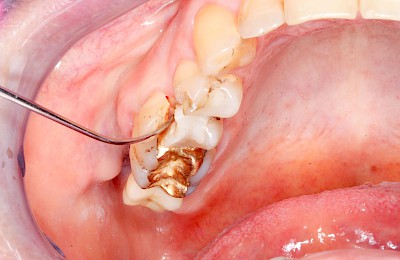

Nach einem Sturz auf das Gesicht, nach einem Schlag auf den Mund bzw. auf die Zähne oder auch beim Kauen (Beissen auf Lippen, Zunge oder Wange) kann es neben sichtbaren Auffälligkeiten im Gesicht und an den Lippen auch zu Verletzungen im Bereich der Zähne, der Zunge oder der Mundschleimhäute kommen. In allen diesen Fällen sollte ein Zahnarzt gerufen werden.

Die folgenden Auffälligkeiten und Probleme können hin und wieder in Folge eines Sturzes, eines Unfalls oder einer Verletzung beobachtet werden: